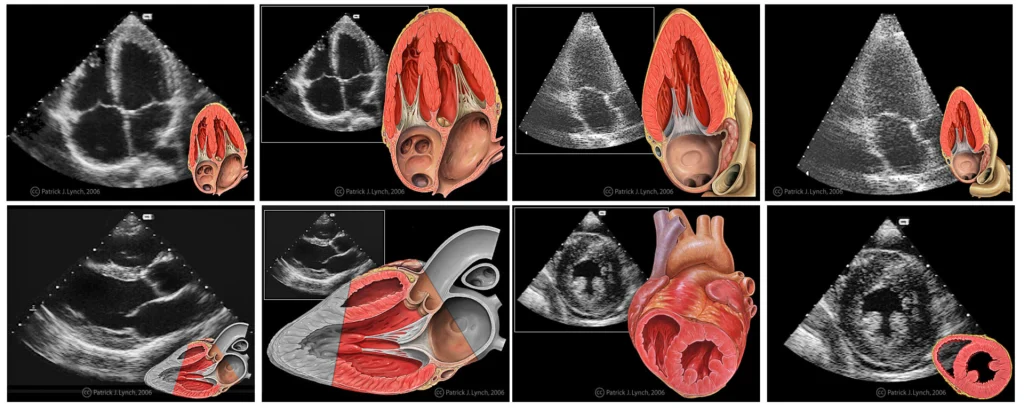

A grid of echocardiogram images paired with anatomical heart illustrations, showcasing heart structure and function.

An echocardiogram is a diagnostic test that uses high-frequency sound waves, or ultrasound, to create live images of your heart. These images allow healthcare providers to evaluate the heart’s structure, functionality, and blood flow in real-time. Unlike other imaging methods like X-rays, echocardiograms do not involve radiation. Thus making them a safe and widely used option for both routine checkups and complex diagnoses.

The procedure involves a device called a transducer, which emits sound waves that bounce off the heart’s structures. These echoes are then converted into detailed images by a computer.